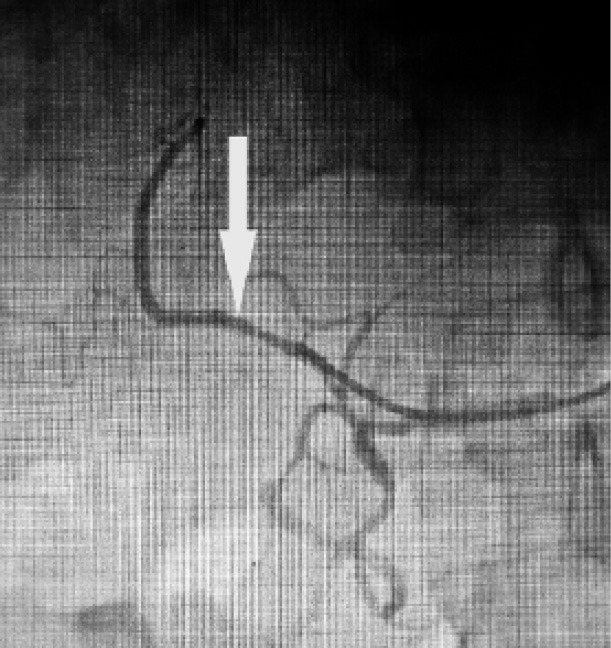

Процедуре введения аутологичных мезенхимальных стволовых клеток печени предшествовала госпитализация пациента с целью выполнения лапароскопии с забором ткани печени, из которой в последующем выделялись мультипотентные мезенхимальные стромальные клетки (мМСК). Из биоптата печеночной ткани путем ферментирования коллагеназами I и IV с последующей селекцией по способности к адгезии были выделены мМСК, способные при обработке дифференцировочными коктейлями переходить к экспрессии генов, специфичных для гепатоцитов. Выделенные клетки были культивированы, проверены на отсутствие бактериальной, вирусной и грибковой контаминации, генетически идентифицированы, оценена их функциональная активность и клеточный состав. Полученные клеточные структуры были отмечены наночастицами оксида железа [12] с целью их последующей визуализации в организме пациента. После того как клеточные культуры были подготовлены, пациент был повторно госпитализирован для проведения процедуры их введения. Клеточные структуры вводились в артериальное русло печени. Предварительно пациенту выполнялась целиакография с последующей селективной ангиографией артериального русла печени. Аутологичные мезенхимальные клетки печени, предобработанные дифференцировочным коктейлем в комбинации с необработанными клетками (3:1), были введены в правую печеночную артерию в количестве 20 миллионов (15 миллионов обработанных+5 миллионов необработанных), рисунок 1. На этом процедура была завершена. В послеоперационном периоде каких-либо осложнений выявлено не было.

Рис. 1. Селективная ангиография артериального русла печени с введением клеточных структур в правую печёночную артерию